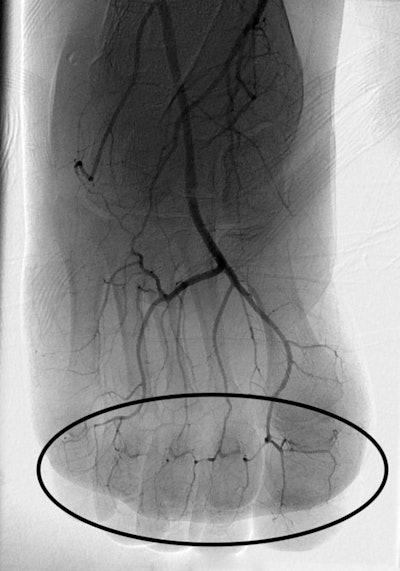

DSA image of right foot obtained approximately 24 hours after infusion of 1 mg/h intraarterial tPA, concomitant systemic IV heparin (500 U/h), and daily 81 mg aspirin shows marked interval pedal digital revascularization, with reappearance of digital arteries (oval).

DSA image of right foot obtained approximately 24 hours after infusion of 1 mg/h intraarterial tPA, concomitant systemic IV heparin (500 U/h), and daily 81 mg aspirin shows marked interval pedal digital revascularization, with reappearance of digital arteries (oval).Of the 209 patients, 116 were treated with intra-arterial tPA and 77 with intravenous tPA; the reasons for these treatment decisions were not clear in the studies, Lee and Higgins wrote. Patients were also treated with therapeutic heparin, warfarin, nonsteroidal anti-inflammatory drugs, pain management, and light dressings with topical antimicrobial agents, the authors noted.